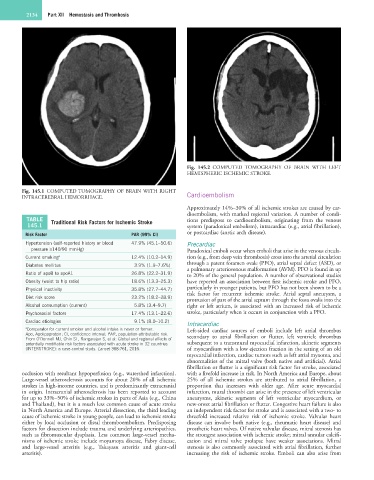

Fig. 145.2 COMPUTED TOMOGRAPHY OF BRAIN WITH LEFT

HEMISPHERIC ISCHEMIC STROKE.